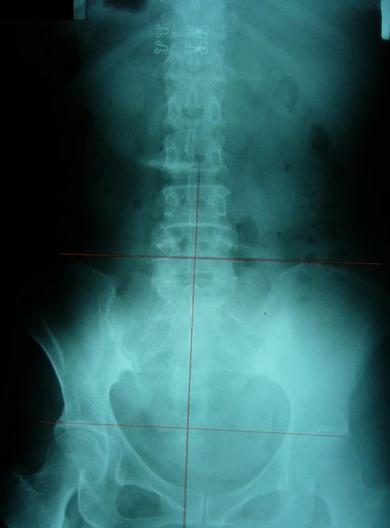

一般最常见到骨盆歪斜的案例包括产后骨盆不正、车祸、撞击、跌倒、姿势不良…等等造成。骨盆歪斜的典型症状包括腰部、髋臀部、腿、膝部疼痛。列举三个自在美国取得脊医执照以来曾经处理过骨盆歪斜相当明显的案例。都是骨盆部位曾经遭受撞击。案例A是超过十年以上的陈年车祸旧伤、另一案例B是急性摔伤(两天内)的案例。两者的X光片都依照美国脊医X摄影方式采站姿摄影评价。借此同时评价骨盆在重力(gravity)影响下的反应。也可以泯除躺歪斜摄影而造成图像不正的情况。最简单的评价要点包括骨盆高低边?中线是否穿越耻骨联合?左右两边是否对称?我简单的几条线一画,相信连外行人也可以看出明显的骨盆歪斜的情况。案例A属陈旧性伤害在调理约两个月后明显降低腰臀腿部的不舒服。而案例B属急性伤害,案例B在调理近三周后骨盆疼痛由原先的持续疼痛降低为完全不痛。之后的骨盆X光摄影重新评价也显示骨盆旋转的问题大幅改善。

严重不对称案例,伴随腰椎向左倾斜